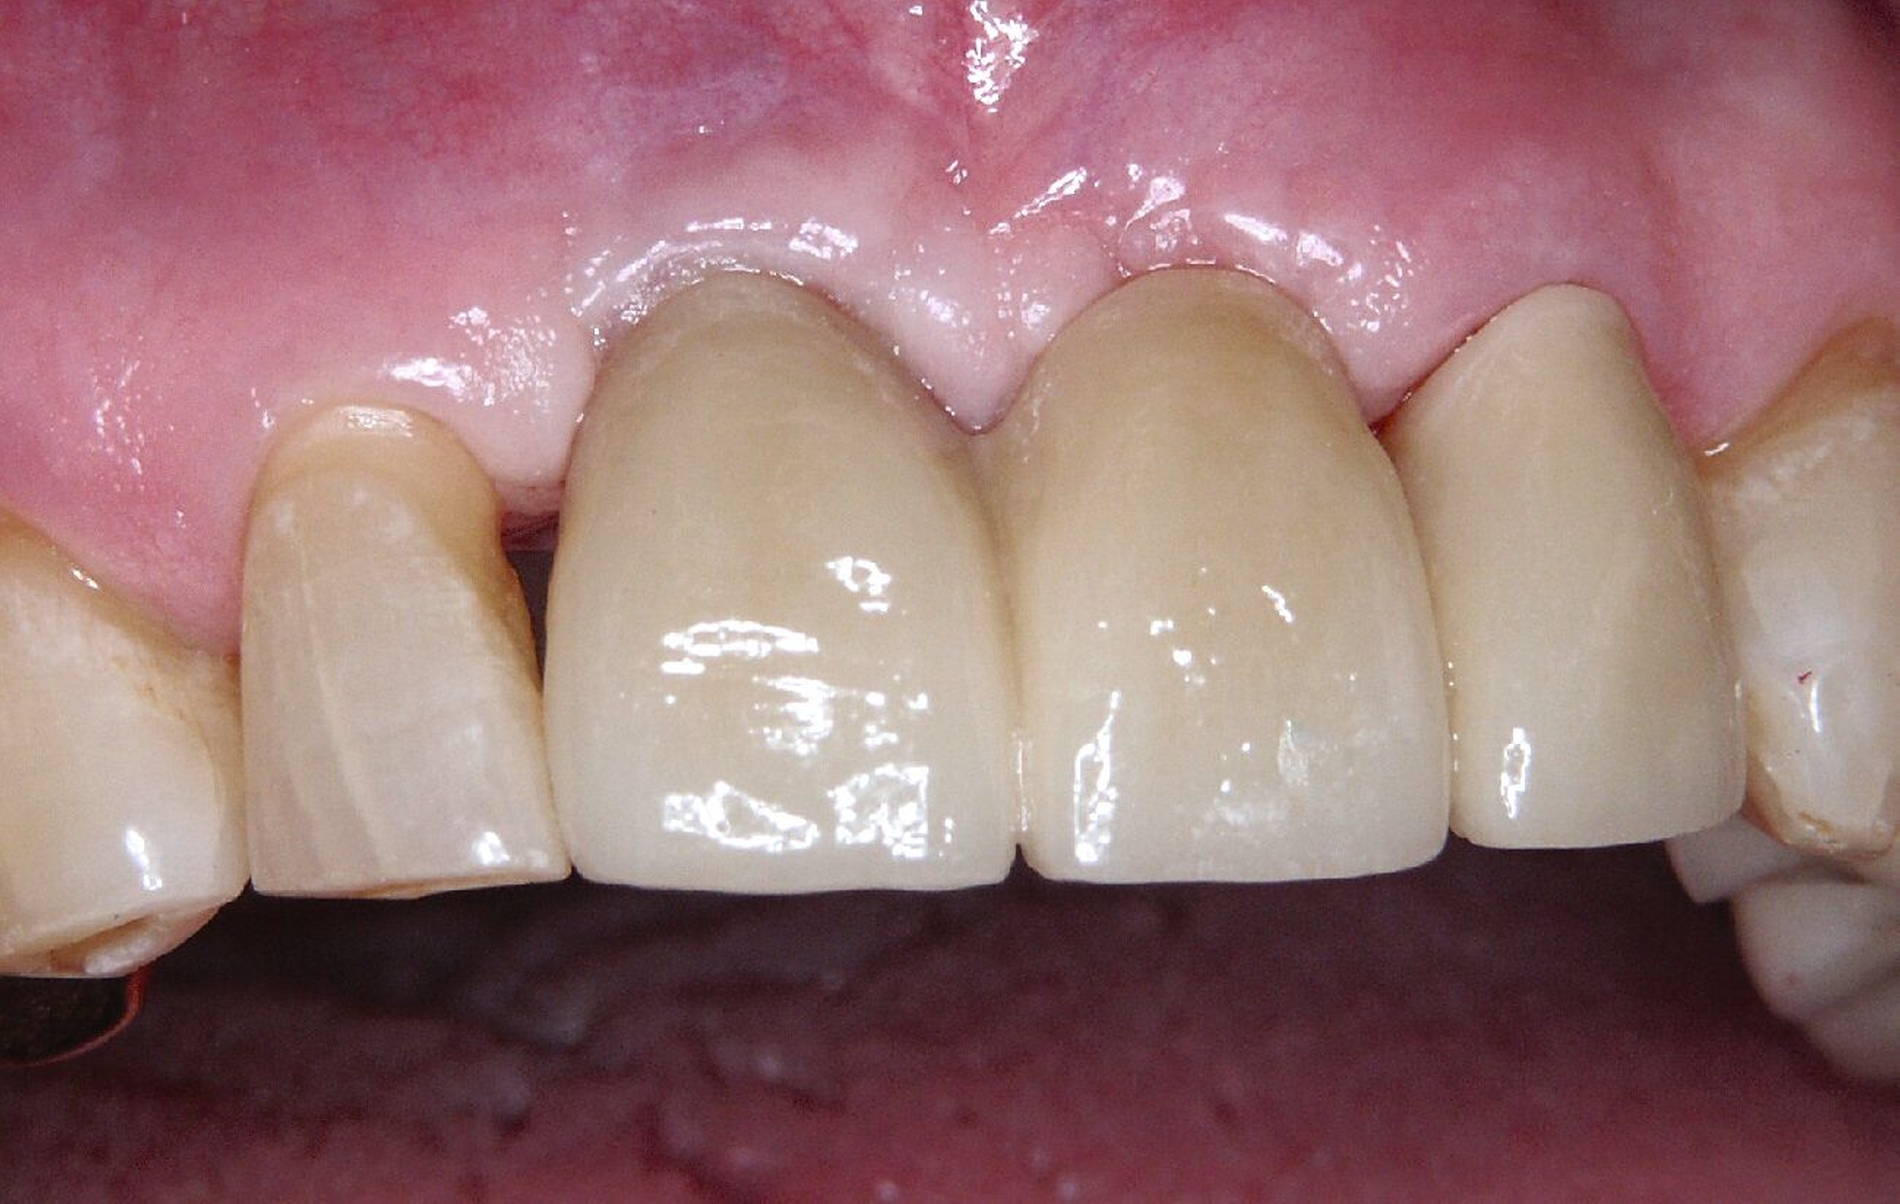

Ursprünglich waren bei dieser Patientin nach einem Frontzahntrauma vier Implantat-gestützte Kronen geplant. Nach dem frühen Verlust des Implantats in regio 21 während der Einheilzeit wurde dann eine auf drei Implantaten abgestützte Brücke eingegliedert. Das bestehende vertikale und horizontale Weichgewebsdefizit wurde bei der verschraubten Implantatbrücke durch aufgebrannte rosafarbene Keramik kaschiert (Abb. 3a). Funktionell war die Brückenversorgung über viele Jahre erfolgreich und zeigte keinerlei Lockerungsgrad. Trotz guter Mundhygiene war in Kontrollsitzungen ein kontinuierlicher Knochenabbau an allen Implantaten festzustellen (Abb. 3b). Zur Vermeidung eines weiteren Knochenverlusts fiel circa 15 Jahre nach der Erstversorgung die Entscheidung zur Explantation. Zu diesem Zeitpunkt war die Patientin 55 Jahre alt.

Nach dem Abschrauben der Suprastruktur (Abb. 3c und 3d) wurden alle Implantate unter Lokalanästhesie mit einem passenden Trepanbohrer umbohrt und ohne Lappenbildung entfernt. Die temporäre Lückenversorgung erfolgte mit einer herausnehmbaren Prothese, die über Gussklammern am Restgebiss abgestützt war.